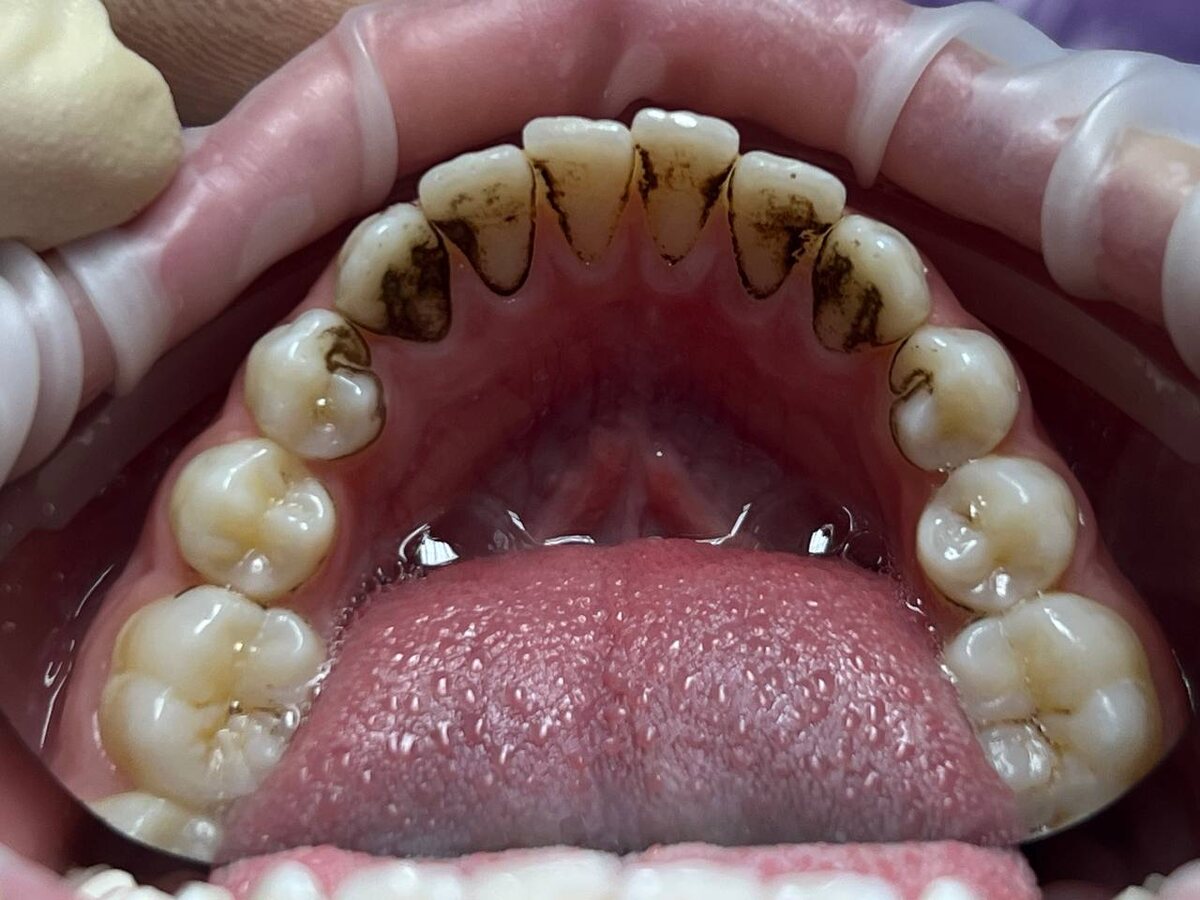

В случае, если на зубах ребенка появился плотный тёмный налёт, который невозможно удалить с помощью обычной щётки или зубной пасты, с высокой вероятностью речь идет о налёте Присли. Это явление достаточно распространено среди детей и может вызывать беспокойство у родителей. Важно понять, что представляет собой этот налёт, следует ли его останавливать и какие шаги предпринять для его устранения.

Налёт Присли — это уникальная форма зубного налёта, наблюдаемая у некоторых людей, преобладающе в детском возрасте. Характерные черты налёта:

- Плотная структура и тёмный оттенок — от коричневого до почти черного.

- Образуется в зоне дёсен и на внешней поверхности зубов.

- Не поддаётся удалению стандартными средствами гигиены полости рта.

- Вызывает эстетический дискомфорт, однако здоровье зубов может оставаться в норме.